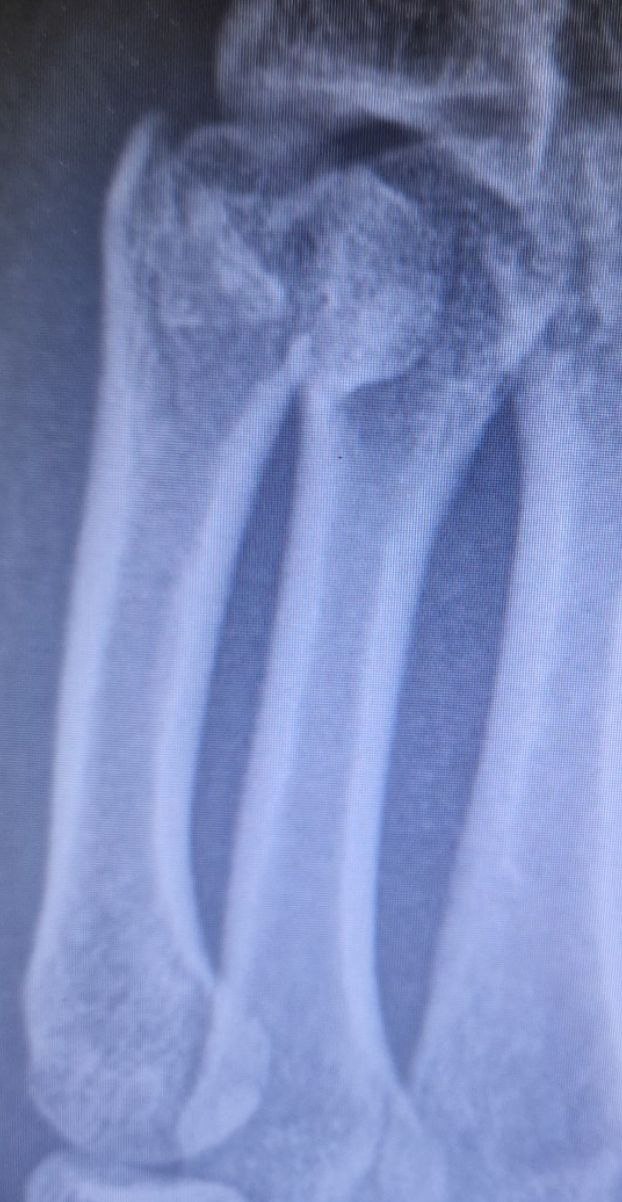

Fracture des métacarpiens

Fracture M5

Col M5

Col M5: tolérance de 40° de bascule palmaire (selon les patients!). [Jouve] tolère 30° pour les enfants.

Bien dépister un Tr rotatoire et un racourcisst.

Attelle en intinsèque plus avec syndactylie des 4 et 5eme doigt laissant libres les IPP et le poignet. Rx contrôle J8.